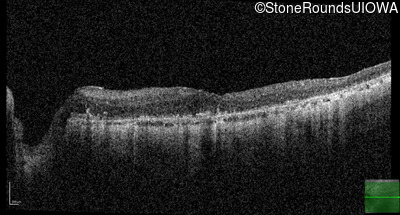

This 81 year old man began using a flashlight to read menus in his 40's. At age 75 his ophthalmologist noticed abnormal fundus findings and referred him to a retina specialist.

| Age at visit: 81 years |

| Age at visit: 82 years |

| Age at visit: 83 years |

| Age at visit: 84 years |

| Age at visit: 85+ (Visit 1) |

| Age at visit: 85+ (Visit 2) |